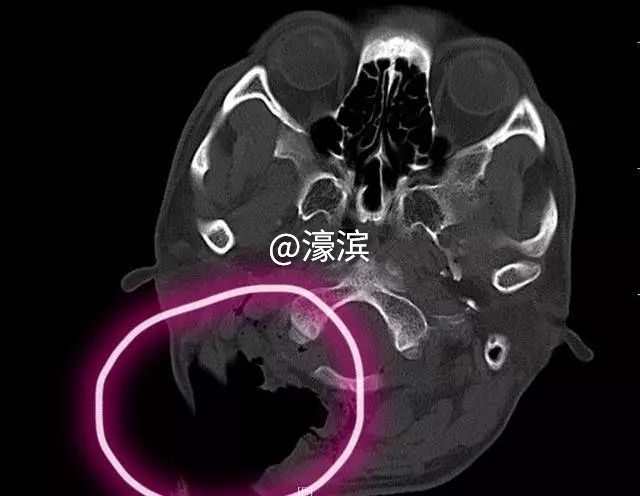

CT图上,患者的伤口很惊人

玻璃块插入后颈,形成10厘米大窟窿

患者来到急诊已是凌晨两点,经过CT检查,医生发现右侧颈部一个大窟窿,创面长达10厘米,颈部创面深入至椎体,但幸运的是未伤及脊髓。考虑病情复杂,急诊医学科找耳鼻咽喉-头颈外科、骨科、普外、介入与血管外科、神经外科等科室紧急会诊,最终决定立即手术。